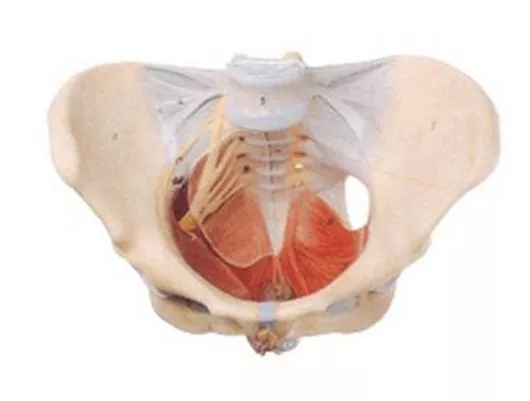

什么是盆底肌?

盆底肌是指封闭骨盆底的这一部分肌肉群。它像一张吊网一样托着我们的尿道、膀胱、直肠、阴道、子宫、前列腺等脏器。使这些脏器维持其正常的位置,良好的行使其功能。

女性盆底肌群大致分为三个部分:肛门附近的括约肌、阴道附近肌肉群以及控制尿道的肌肉群。